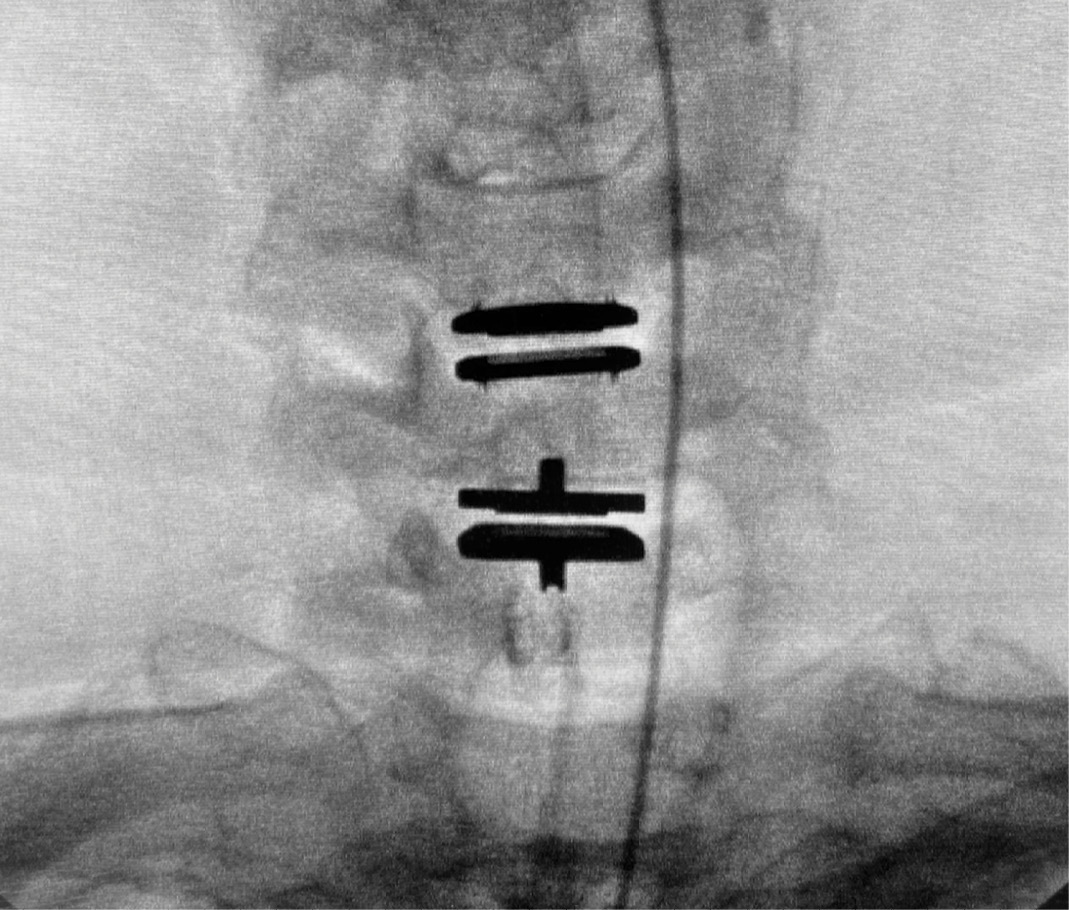

During intra-operative trialing after discectomy and foraminotomies, I felt that the best fit at the C6-7 level was with a prodisc C SK—6mm tall by 18mm deep (Figure 6a). I then performed the discectomy and trialing at the C5-6 level and felt that the prodisc C Vivo was a perfect fit here (Figure 6b).